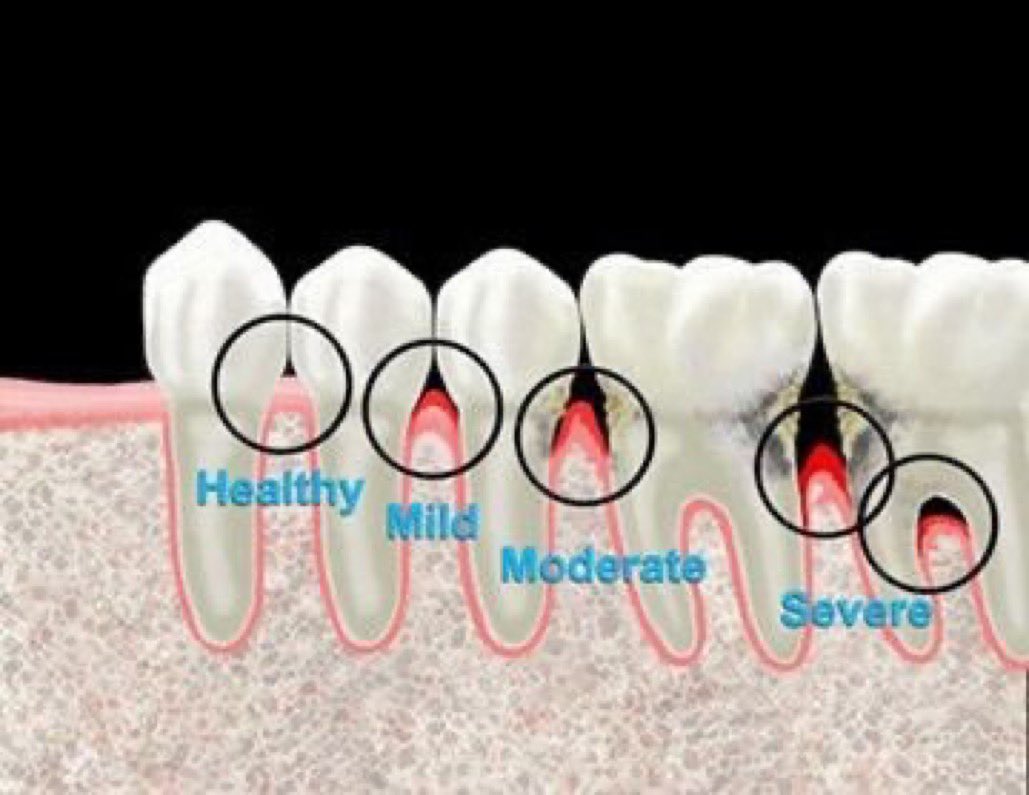

مراحل التهاب اللثة:

التهاب اللثة الخارجي(مرحلة١):

- الانتفاخ

-الإحمرار

-النزف من اللمس او التفريش

-الألم وتختلف درجته من شخص لآخر

-سهل العلاج ويختفي تماماً بإزالة المسبب والعناية بنظافة الاسنان والاهتمام وعدم إهمال الخيط السني

التهاب اللثة العميق(مرحلة٢):

-تآكل بسيط في اطراف العظم الداعم للآسنان وقد(غالبا)يكون مصحوب بعلامات من التهاب اللثة الخارجي

اعراضه قد تشابه المرحلة (١) وقد لا يكون ظاهرا

-يمكن علاجه إذا اكتشف باكرا وإيقاف تقدمه.